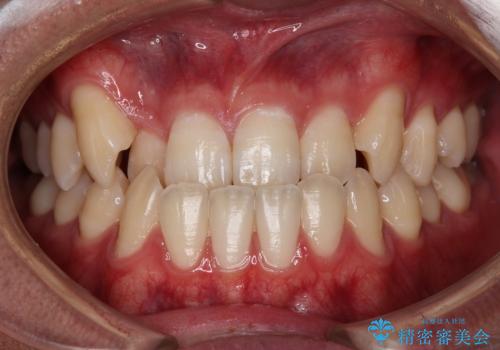

[ 奥歯の歯周病 ] エムドゲインを用いた再生治療

![[ 奥歯の歯周病 ] エムドゲインを用いた再生治療の症例 治療前](https://seimitsushinbi.jp/wp/wp-content/uploads/2025/09/da7ea9f28849677c773d656ce0944c22-500x350.jpg?v=1757645152)

![[ 奥歯の歯周病 ] エムドゲインを用いた再生治療の症例 治療後](https://seimitsushinbi.jp/wp/wp-content/uploads/2025/09/cd7402647dc4e0e897f31dff1860179d-500x350.jpg?v=1757645235)

メンテナンスで日々のブラッシングの再確認